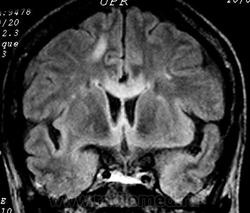

ГМ. Рассеянный склероз 2. +

Рассеянный склероз